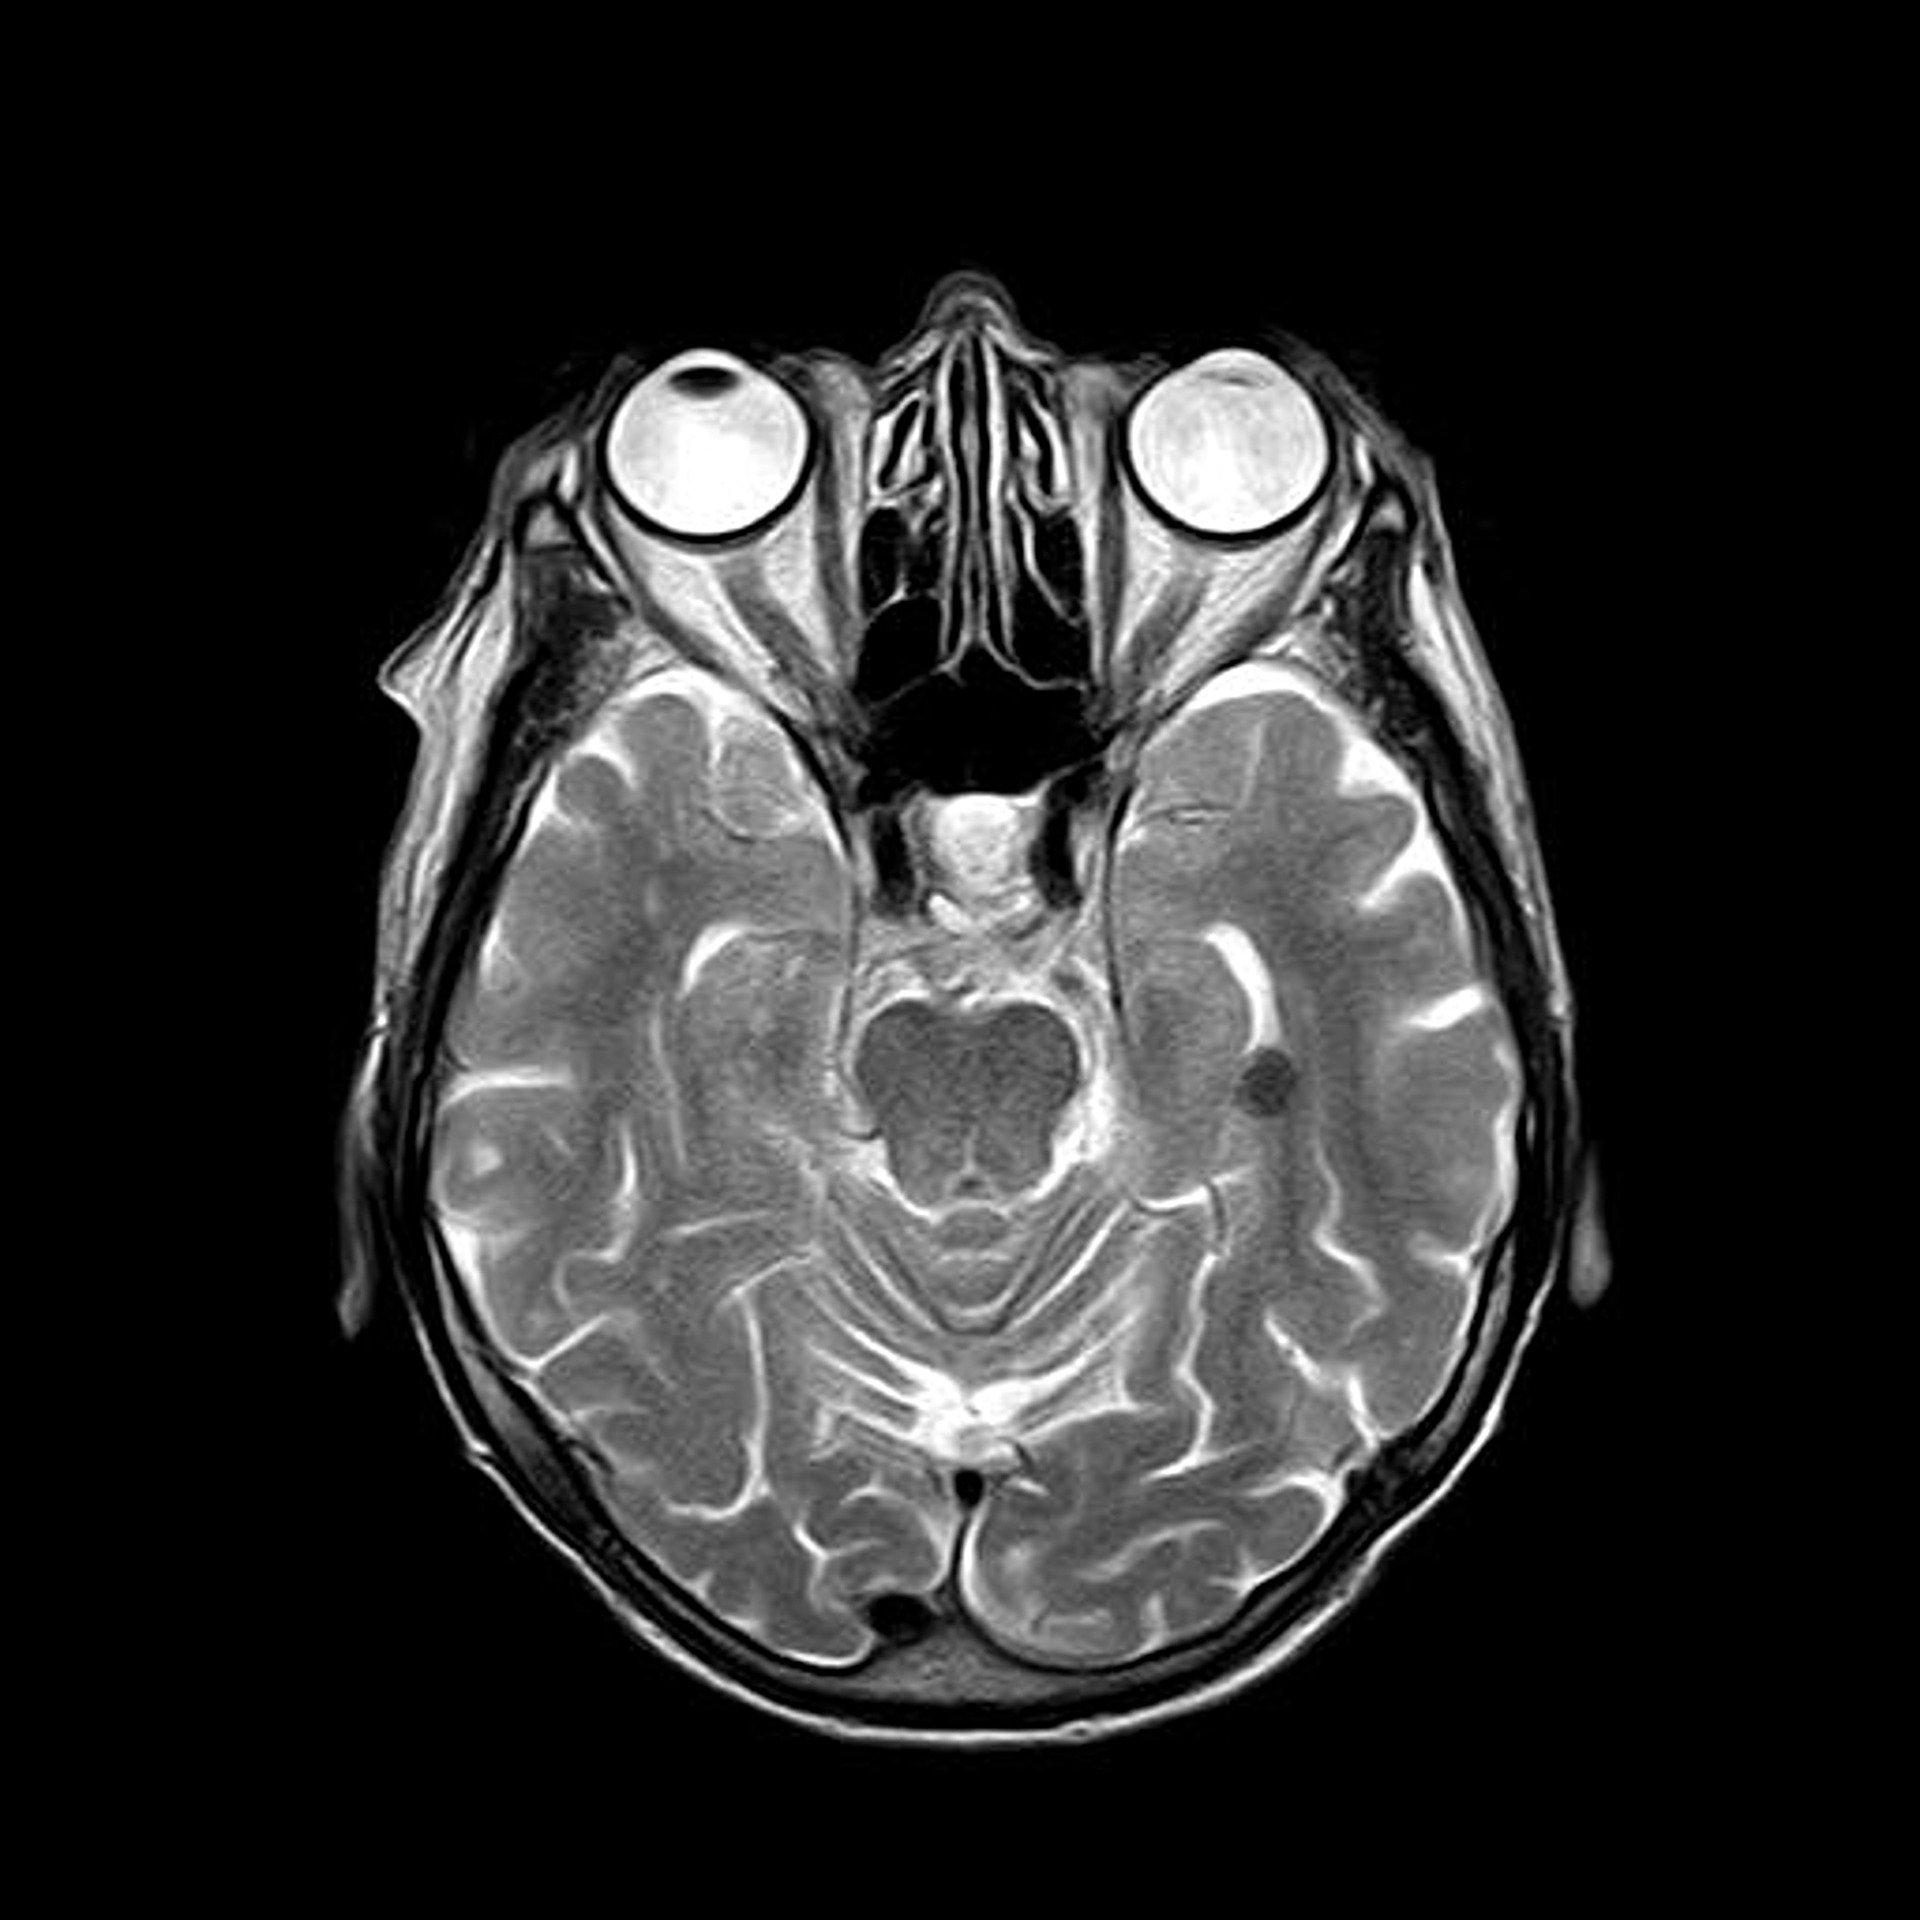

MRI photo of skull and internal parts.